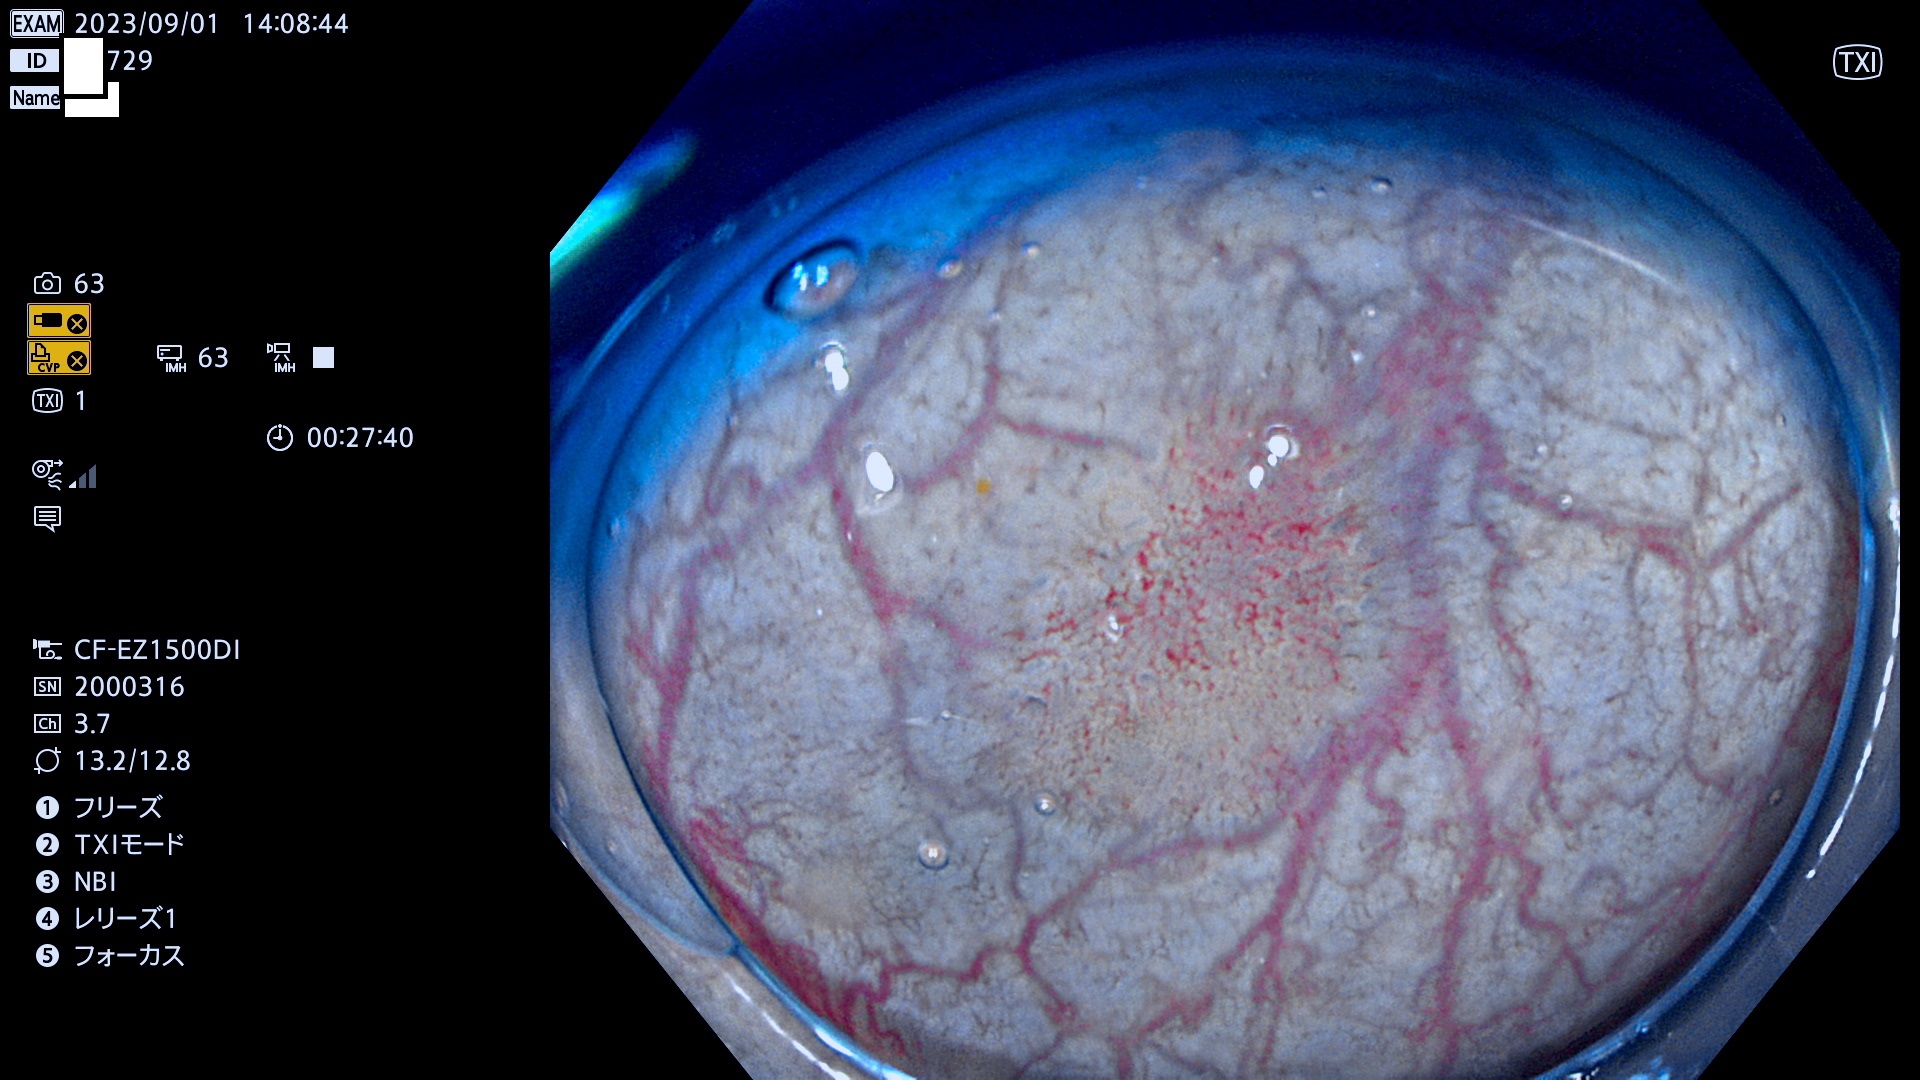

表面型腺腫(Flat Adenoma)の中で、完全に平坦な物をUb、陥凹している物をUcと呼びます。平坦隆起型(Ua)よりも、発見が難しく危険な病変です。このタイプは「内視鏡後・大腸癌の重要犯人」であり、この発見率は「腺腫発見率」よりも、重要な意味があります。

専門的)何故、陥凹していると危険? 癌遺伝子の変異が蓄積すると細胞分裂が盛んになり隆起するのでは?と通常は思われるでしょう。しかし実際は逆です。これは2022年の記事にある「細胞はストレスに直面したら細胞分裂を止める(細胞老化に入り休眠する)という生命の基本的現象」によるものです(Oncogene Stress)。細胞老化を起こすのが癌抑制遺伝子で、この安全装置(ブレーキ)が壊れると癌になります(休眠からの覚醒)。ですから陥凹は「まだ癌では無いが癌化の直前」を意味します。特に「小サイズなのに陥凹している」病変は短期間に腫瘍進化(⇒2021年記事)が起きたことを意味します(=ゲノム不安定性

毎週の検査(木・金・土・日)に発見されたUb、Uc型・腺腫を、その週の日曜の夜にUPし1週間、提示します。

抽出の対象期間 2023年8月31日(木)〜9月3(日)の4日間(48件の検査)12件